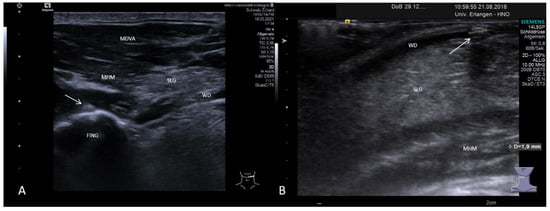

3.3.2. Obstructive Sialadenitis Caused by Sialolithiasis

3.3.3. Non-Sialolithiasis-Caused Unspecific Sialadenitis with Sialodochitis and/or Duct Stenosis with Primary or Secondary Obstruction